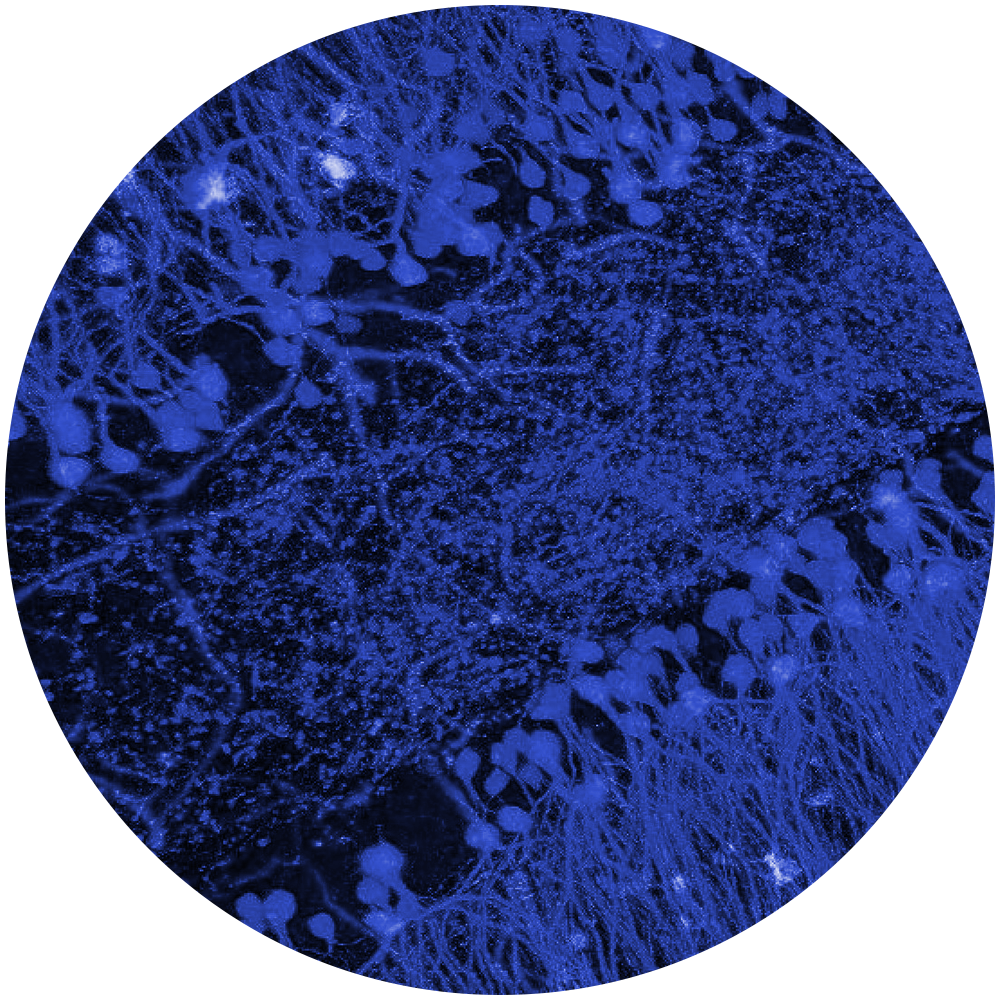

Our interdisciplinary team of investigators collaborated to tackle some of the most confounding and disabling medical conditions.

Our innovative discoveries are fueled by well-funded interdisciplinary collaborations. These partnerships accelerate the development of therapeutics and allow us to deepen our understanding of brain function and the processes that go awry in neurological diseases.